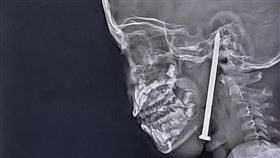

7歲男童玩耍跌倒 「8公分」鐵釘灌入腦門

印度一名7歲男童日前在玩耍時跌倒,一根長達8公分的鐵...

連生3女尪崩潰 孕婦拿5公分釘插腦

台灣性別平權意識已經普及,且傳統重男輕女的觀念也已不...